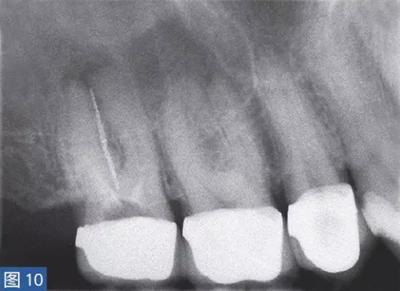

慢性根尖周膿腫(圖10 和11)是由長(zhǎng)期持續(xù)的炎癥引起的。膿液穿通骨和口腔黏膜,并通過(guò)口腔黏膜或上皮的瘺管流出。這些通到表皮的瘺管通??赡茏鳛槠つw損傷而被錯(cuò)誤處置。此外,瘺管也可能存在于牙周并通過(guò)齦溝引流。瘺管可以部分或完全地被上皮所包繞,這些上皮又被炎性結(jié)締組織包圍。

臨床診斷顯示牙髓電活力測(cè)試結(jié)果為陰性。除非瘺管閉合,否則叩診和觸診通常都不會(huì)引起疼痛。放射學(xué)檢查,根尖周組織表現(xiàn)從無(wú)變化到發(fā)生明顯變化。

圖10:17 牙齒CAA。術(shù)前放射學(xué)檢查,利用牙膠尖顯示瘺管。患者因17 牙齒局部瘺管而前來(lái)就診,訴無(wú)特殊臨床癥狀。

圖11: 17 牙齒CAA。根管治療12 個(gè)月后。